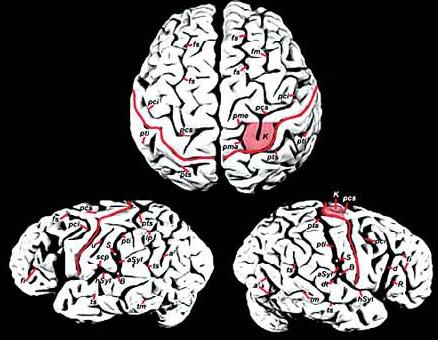

最近,从医学专业杂志《刺针》上传来一则好消息:麻省理工学院著名认知科学家斯帕克初步认定:爱因斯坦的大脑结构与其特殊功能之间存在某种内在联系。斯帕克发现,就在位于齐耳高度、从脑前延伸至后部2/3的下顶叶处,即人脑处理数学思维、三维形象和空间关系等的关键部位,“爱脑”确实与“凡脑”不同:后者的顶叶和颞叶之间通常由“西尔维裂沟”所分裂,形成一道脑上天堑;而“爱脑”的裂纹却在接近顶叶处戛然而止,并急转直上,绕过顶叶不再分裂。于是“天堑变通途”,保持了顶叶的相对完整,而且顶盖骨也模糊不见,因此整个大脑顶叶沟壑纵横,路径曲折,密密麻麻覆盖全脑,联结面积比普通人大约15%。这意味着,更多的脑细胞或神经元更易于联系,可以更好地协调工作。

随后,斯帕克又在《纽约时报》上发表专文,阐明大脑顶叶即每一大脑半球顶端的后部象限,位于初始视觉和体感之间的地方,是空间感的区域。而这也正是爱因斯坦借助“顶叶智力”确定各类事物的部位,从而在下侧小叶或骨叶低处隆起专司抽象数学和空间推理的超凡直觉与优异数值演算能力的区域。

关于爱因斯坦大脑“下叶区智慧”的研究也有新的发现。不久前,由加拿大麦克马斯特大学教授桑德拉,威尔特森领导的研究小组发现,位于爱因斯坦后脑左右半球的上部顶下叶区域比常人大15%,其机理非常发达。这项研究成果发表在著名医学杂志《柳叶刀》上,认为爱因斯坦的天才是天生的,并非全靠后天用功求学得来,证实后天的努力虽然也能成才,但天生天才也是事实。大脑中负责视觉思考和空间推理的顶下叶区域发达,对一个人的数学思维、想象力以及视觉空间认识都发挥着重要作用。这一研究解释了为何爱因斯坦有独特的抽象思维与过人的空间认知能力——左右半球的上部顶下叶区域比常人要大。

斯帕克指出,爱因斯坦大脑左右上部顶下叶区一般大,二者都大于常人15%,而脑重不增。有了这个完整、宽大的小叶,即可通过千百万突触所构成的微循环,容纳更丰富也更紧凑的空间与数学推理的逻辑思维线路。因此,思维敏捷、思路活跃的爱因斯坦之所以成为绝世天才,很可能是胎儿发育早期自然形成的。

特异之二:爱因斯坦大脑不仅在左右上部顶下叶区比一般人大15%,更不寻常的是顶下小叶区缺少常人都有的一条特殊的裂缝,导致两块关键的脑部区域成为一个整体。有了这个完整、宽大的小叶,即可通过千百万突触所构成的微循环,容纳更丰富也更紧凑的空间与数学推理的超凡逻辑思维缨路。

特异之四:一般人的大脑里有一条叫做“外侧裂”的脑沟穿过这里,沟的尾稍嵌入一块名为“缘上回”的区域。而在爱因斯坦的大脑照片上则显示,他的“外侧裂”在进入顶叶下部区域之前就与另一条脑沟合并,“缘上回”也显得更为完整。维特森认为,一般情况下,大脑中神经连接密集的地方形成凸起的脑回,而神经连接比较稀少的地方则凹下变成脑沟。爱因斯坦戛然而止的外侧沟,正好说明他的顶叶下部区域比一般人的神经连接更密集。

特异之五:这是迪安·法尔克在《进化神经科学前沿》上发表的最新研究成果。爱因斯坦大脑表层的很多部分没有凹沟,因此神经细胞可以通行无阻地沟通,思维也能够活跃无比。维特森指出,爱因斯坦大脑的顶叶异常发达,在形态上也有特异之处,例如侧脑裂并不明显,特别是左半球。因此顶叶下段皮质中的神经元易于相互联系,使爱因斯坦在视觉、空间认知、数学思考、运动知觉这些认知领域中,表现出超卓的智力。